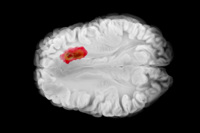

Lessons Learned While Taking Glioblastoma Drug From Bench To Clinic

MimiVax CEO Mike Ciesielski recounts the company's transition from academia to industry, hitting on topics like vendor partnerships, FDA conversations, and manufacturer selection.